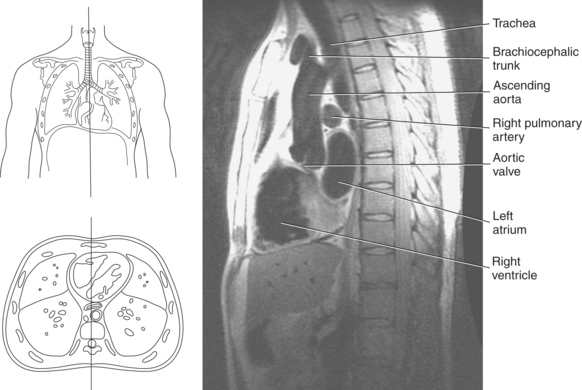

Blood travels to and from the heart through the great vessels, which include the aorta, pulmonary arteries and veins, and superior and inferior venae cavae (Figures 6.54 and 6.55). The aorta is the largest artery of the body and can be divided into the ascending aorta, aortic arch, and descending aorta. The ascending aorta begins at the base of the left ventricle at the level of the sternal angle, then curves superiorly and posteriorly as the aortic arch over the root of the left lung. The top of the aortic arch is approximately at T3 (Figures 6.56 and 6.57). The arch continues as the descending aorta posterior to the left bronchus and pulmonary trunk, on the left side of the vertebral body of T4 (Figures 6.58 and 6.59). The descending aorta passes slightly anterior and to the left of the vertebral column as it descends through the thoracic and abdominal cavities (Figure 6.60). While in the thoracic cavity, the descending aorta is commonly called the thoracic aorta, and while in the abdominal cavity, it is called the abdominal aorta. The pulmonary trunk is the origin of the right and left pulmonary arteries and lies entirely within the pericardial sac. It arises from the right ventricle and ascends in front of the ascending aorta, courses posteriorly and to the left, where it bifurcates at the level of the sternal angle (T4) into the right and left pulmonary arteries (Figures 6.61 through 6.63). The pulmonary trunk is attached to the aortic arch by a fibrous cord called the ligamentum arteriosum, the remnant of an important fetal blood vessel (ductus arteriosus) that links the pulmonary and systemic circuits during fetal development (Figures 6.54 and 6.61). The right pulmonary artery courses laterally, posterior to the ascending aorta and superior vena cava, and anterior to the esophagus and right mainstem bronchus, to the hilum of the right lung. At the root of the right lung, the right pulmonary artery divides into two branches, with the lower branch supplying the middle and inferior lobes and the upper branch supplying the superior lobe (Figures 6.61 through 6.64). The left pulmonary artery, shorter and smaller than the right, is also the most superior of the pulmonary vessels. It travels horizontally, arching over the left mainstem bronchus, and enters the hilum of the left lung just superior to the left mainstem bronchus (Figures 6.61 through 6.64). Within the lungs, each pulmonary artery descends posterolateral to the main bronchus and divides into lobar and segmental arteries, continuing to branch out and to follow along with the smallest divisions of the bronchial tree (Figures 6.61 and 6.64). Located inferior to the pulmonary arteries are the four pulmonary veins, two each (superior and inferior) extending from each lung to enter the left atrium (Figures 6.54, 6.55, 6.61, and 6.64 through 6.68). They commence in a capillary network along the walls of the alveoli, where they are continuous with the capillaries of the pulmonary arteries. The venous capillaries merge to form small vessels that unite successively to eventually form a single trunk for each lobe: three for the right and two for the left lung. Frequently the trunk from the middle lobe of the right lung unites with the trunk from the upper lobe, forming just two trunks on the right side prior to entering the left atrium. The right superior pulmonary vein collects blood from the upper lobe segments of the right lung and passes anterior and inferior to the right pulmonary artery, behind the superior vena cava. The right inferior pulmonary vein receives blood from the right lower lobes of the lung and crosses behind the right atrium to the left atrium (Figures 6.61 and 6.69 through 6.71). The left superior pulmonary vein receives blood from the left upper lobe of the left lung and courses anterior and inferior to the left main bronchus as it enters the left atrium. The left inferior pulmonary vein drains the inferior lobe of the left lung and passes toward the left atrium anterior to the bronchi (Figures 6.61 and 6.72 through 6.74). The pulmonary veins course more horizontally than the pulmonary arteries and are ultimately oriented toward the left atrium. At the root of the lungs, the pulmonary veins are anterior to the pulmonary arteries, which are anterior to the bronchus. While within the lungs, the branches of the pulmonary arteries are anterior to the bronchi, which are anterior to the pulmonary veins. The superior and inferior venae cavae are the largest veins of the body. The superior vena cava is formed by the junction of the brachiocephalic veins, posterior to the right first costal cartilage, and carries blood from the thorax, upper limbs, head, and neck (Figure 6.24). As it travels inferiorly, it is located posterior and lateral to the ascending aorta before entering the upper portion of the right atrium (Figures 6.54 through 6.59). The inferior vena cava is formed by the junction of the common iliac veins in the pelvis and ascends the abdomen to the right of the abdominal aorta and anterior to the vertebral column. It passes through the caval hiatus of the diaphragm and almost immediately enters the inferior portion of the right atrium (Figures 6.75 and 6.76).

Figure 6.60 Sagittal, T1-weighted MR scan with aortic arch and descending aorta.

Key: ar, aortic arch; da, descending aorta; mbr, mainstem bronchi; rPA, right pulmonary artery; ab, aortic bulb; la, left atrium; rv, right ventricle.